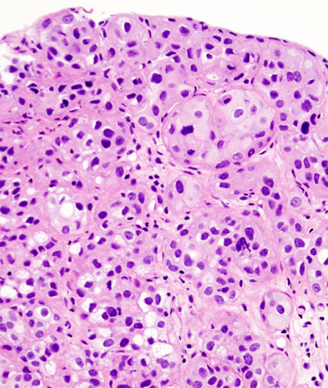

Urothelial carcinoma of the urinary bladder; source: KGH, Wikimedia Commons